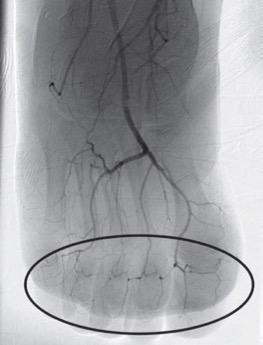

DSA image obtained approximately 24 hours after 1 mg/h IA tPA infusion, 500 U/h heparin via peripheral IV, and daily oral aspirin (81 mg) shows improved perfusion of digital arteries, albeit with suboptimal vascular blush of distal second and third phalanges. Photo courtesy of ARRS

Both digital subtraction angiography (DSA) and triple-phase bone scan were utilized for initial imaging evaluation of patients with severe frostbite injuries.